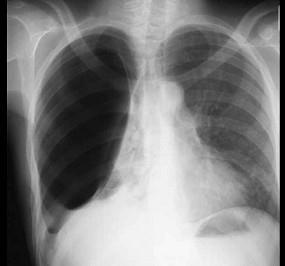

问题 关于急性脓胸的症状、体征及X线表现如图,下列哪项是不正确的? ( )

选项 A、X线检查示肺组织受压,胸膜腔积液呈外高内低的弧形影 B、X线检查示胸膜反应及肋膈窦消失 C、胸部患侧呈浊音,呼吸音减弱或消失 D、大量积液使患侧呈大片均匀阴影,胸膜腔横径变窄,纵隔向患侧移位 E、常在急性肺炎好转后,再出现高热、胸痛、气促、全身乏力等症状

答案 D